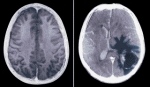

뇌종양, 한방으로 살펴보기

2000년 드라마 '가을동화'에서 한채영의 아역을 맡았던 아역 탤런트 출신 이애정이 뇌종양으로 투병하다 끝내 사망한 것으로 알려져 주위를 안타깝게 하고 있다. 이애정은 지난해 7월 말 두통으로 병원을 찾았다가 뇌종양 판정을 받고 최근까지 투병생활을 해왔고 한...